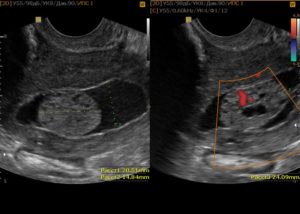

Дополнительными методами исследования выступают УЗИ, рентгенография, сцинтиграфия, МРТ и КТ и прочие.

Лучевая терапия может проходить дистанционно или быть внутриполостной (брахитерапия). Дистанционная лучевая терапия проводиться на линейных ускорителях (на фото).

При помощи брахитерапии возможно проведения больших доз облучения прицельно, в опухолевый очаг, не затрагивая здоровые ткани.

При проведении брахитерапии специальный аппликатор вводится в полость пациентке и посредством его, радиоактивный источник доставляется к цели.

Лучевая терапия в комплексе с химиотерапией становится единственно возможным методом лечения, так как рак носит местно-распространённый характер и не может быть удалён при помощи операции.Современные технологии позволяют использовать несколько видов лучевой терапии: внутриполостная и дистанционная.

Внутриполостная технология подразумевает контактное воздействие с опухолью, такими источниками как кобальт, цезий или иридий.